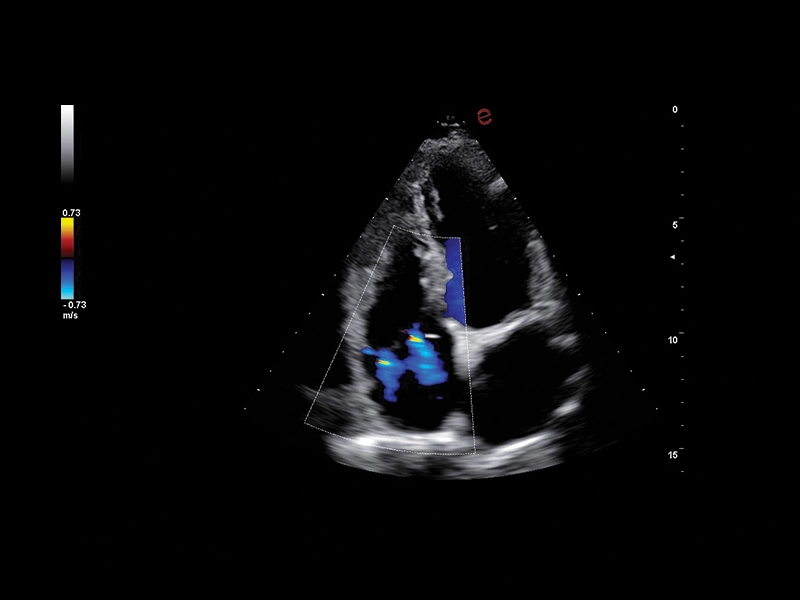

B-mode/M-Mode/CFM/Doppler/Power Doppler/microV

HD Color Doppler (CFM) i Power Doppler (PDI) kao i Directional Power Doppler (DPDI) sa visokom osetljivošću i definicijom.

KLINIČKE SLIKE